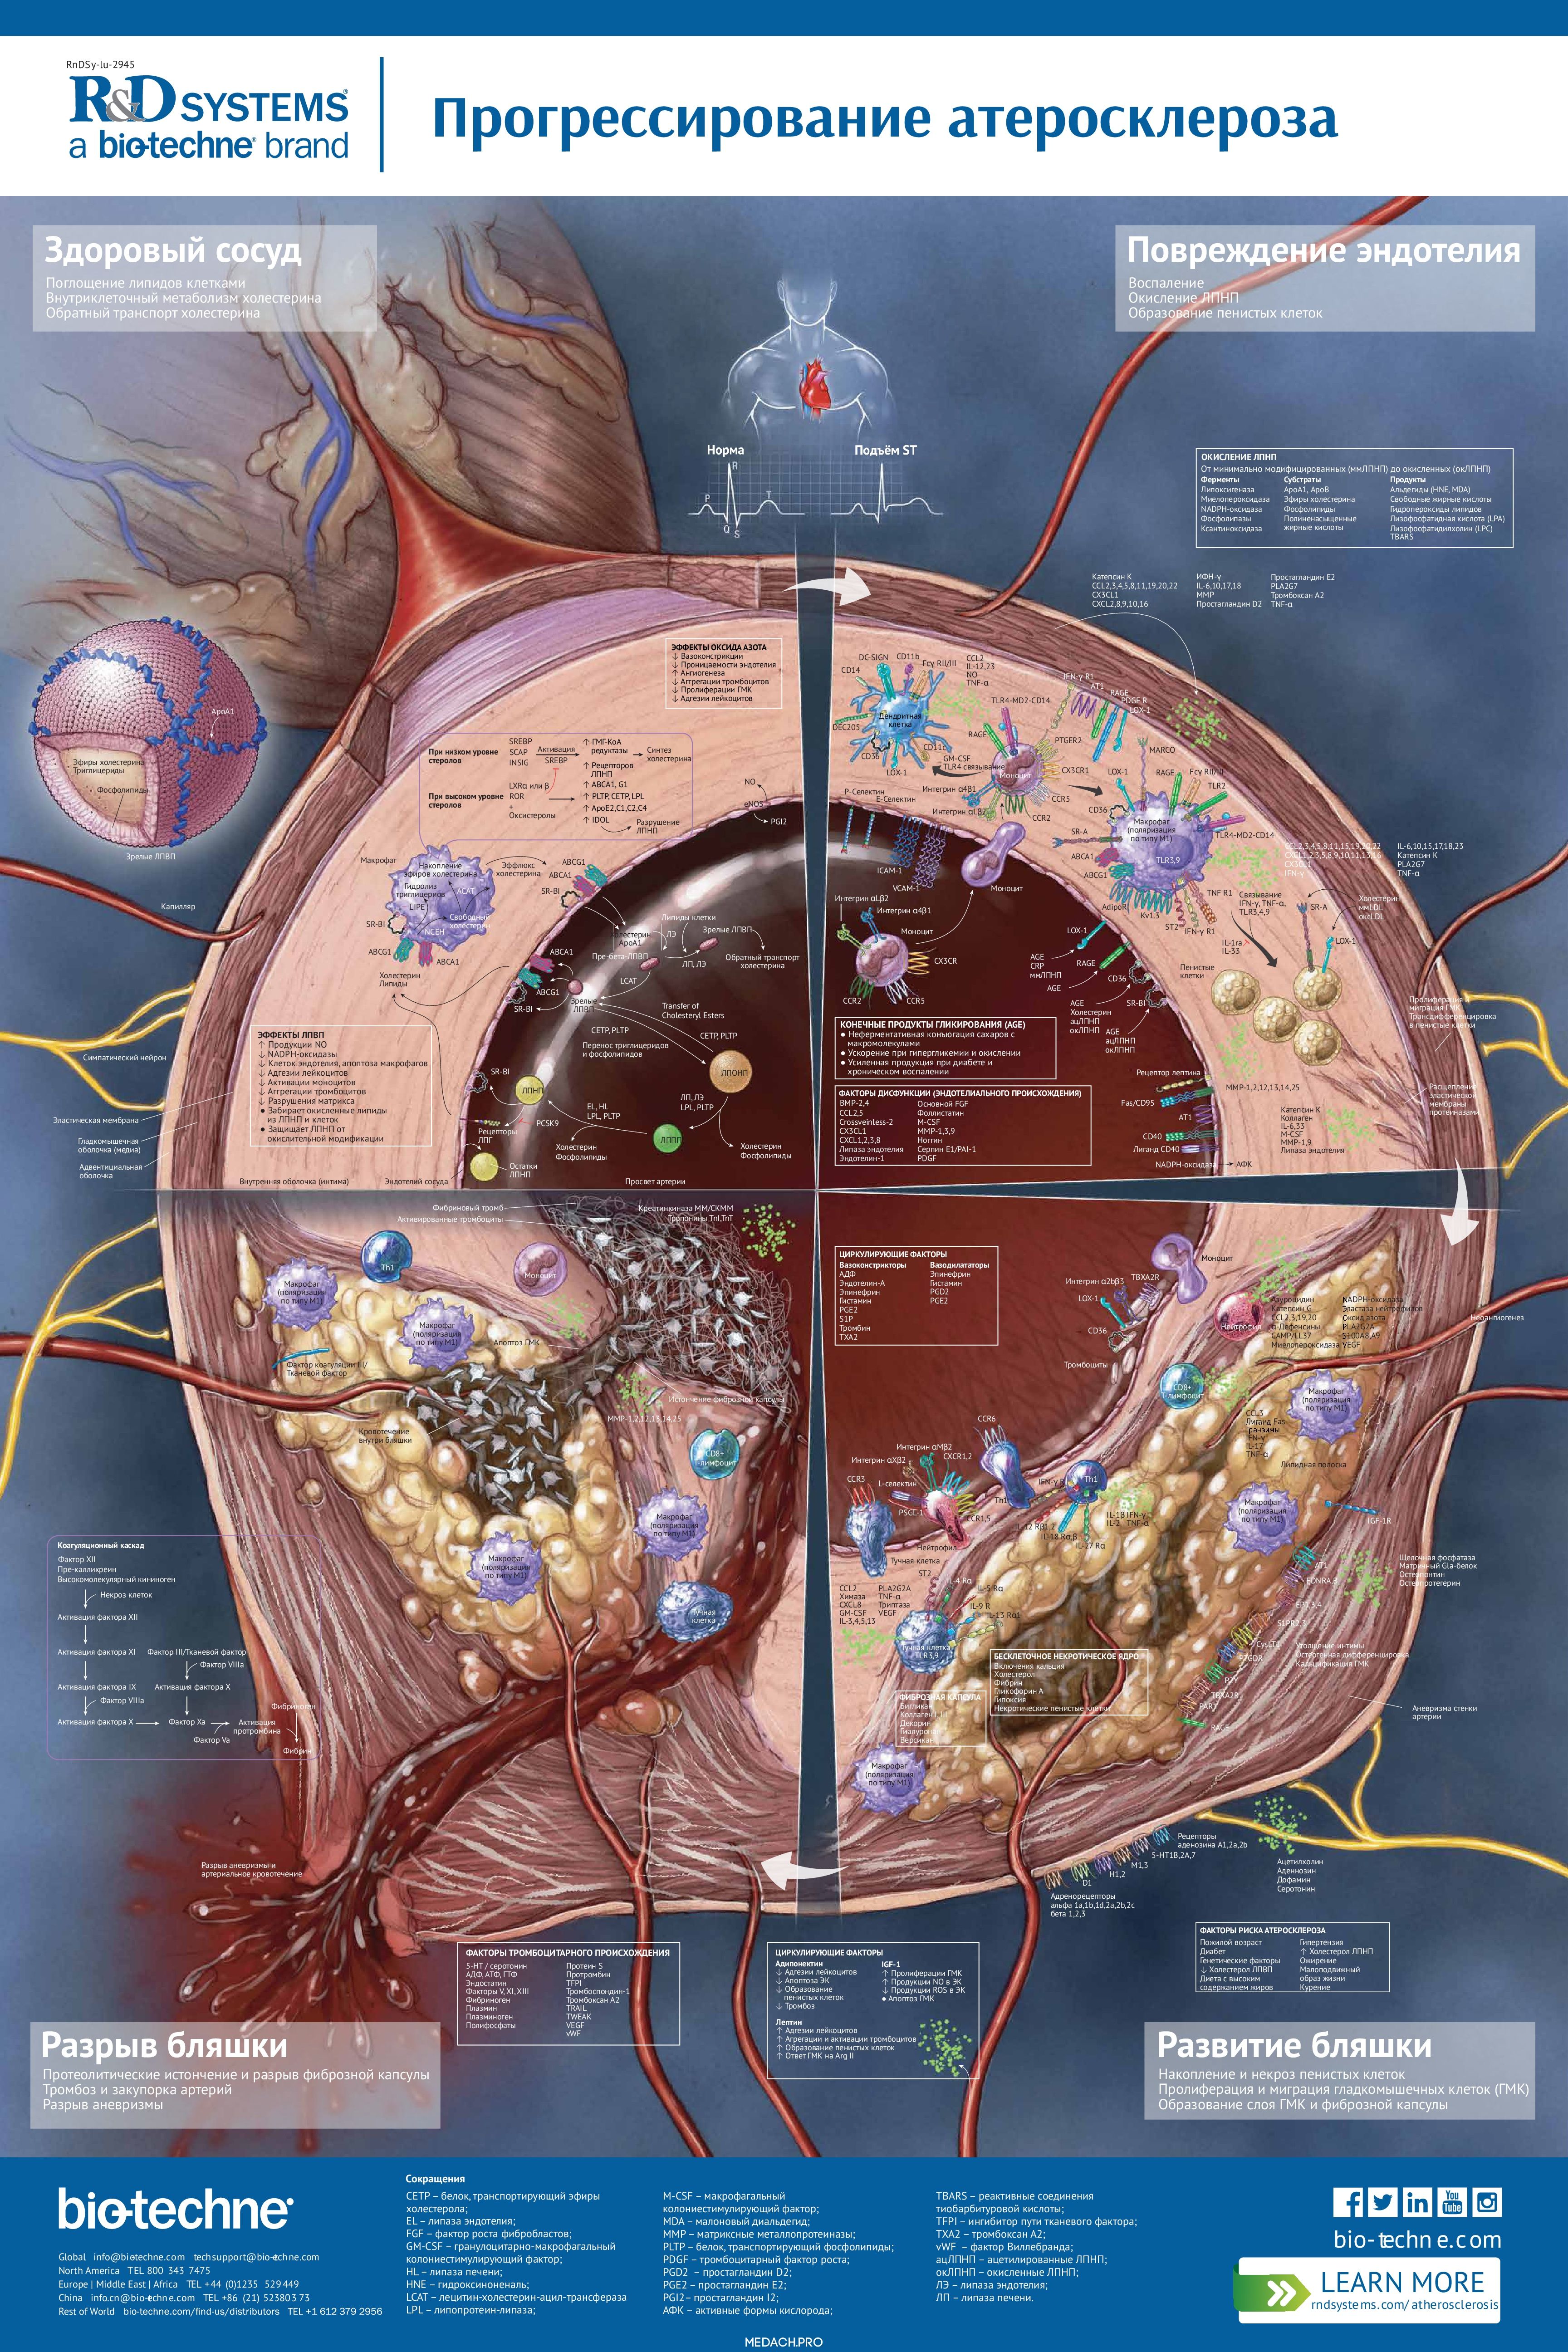

Прогрессирование атеросклероза

Атеросклероз — это хроническое заболевание сосудов, возникающее практически у каждого пожилого человека. Представляем вам плакат, демонстрирующий механизмы тех изменений, которые приводят к образованию атеросклеротической бляшки в стенке сосуда и её разрыву.

Атеросклероз – комплексное многоэтапное заболевание, поражающее сосуды и начинающееся с повреждения их внутреннего эндотелиального слоя. Клетки эндотелия сосудов отвечают на повреждение усилением экспрессии адгезионных белков, медиаторов воспаления и окислительных ферментов. Иммунные клетки прикрепляются к активированному эндотелию и путём экстравазации проникают в интиму, где развивается воспалительный ответ. В результате окисления липопротеиновых частиц ферментами образуются окисленные ЛНП.

Макрофаги интимы сосудов фагоцитируют и накапливают окисленные ЛНП, что стимулирует их превращение в пенистые клетки. Пенистые клетки скапливаются и разрастаются, образуя липидные полоски сосудистой стенки. Гладкомышечные клетки сосудов пролиферируют, мигрируют и секретируют матриксные протеогликаны, формируя защитную фиброзную капсулу вокруг бляшки. Затем они претерпевают частичную трансдифференцировку и приобретают фенотип, схожий с костными клетками. Это ведёт к кальцификации сосудистой стенки и утрате эластичности артерий. Истончение комплекса интима-медиа стенки артерий служит показателем прогрессирования атеросклероза. Кроме того, локальная гиперэкспрессия ангиогенных факторов стимулирует неоангиогенез, обеспечивающий кровоснабжение растущей бляшки.

Гибель пенистых клеток и накопление погибших клеток приводит к образованию внутри бляшки некротического ядра. Усиленная экспрессия протеаз стромальными и иммунными клетками постепенно ослабляет фиброзную капсулу. Истончение фиброзной капсулы ведёт к разрыву бляшки и высвобождению её содержимого в просвет сосуда. Контакт некрозного ядра с кровью вызывает быстрое развитие тромбоза, закупорку сосуда (стеноз) и, как следствие, развитие инфаркта или ишемического инсульта.

В другом варианте развития событий, истончение стенки артерий может приводить к формированию аневризмы и кровотечениям. Развитию атеросклероза способствуют диеты с высоким содержанием жиров, курение, пожилой возраст, гипертензия и мутации в генах, вовлечённых в нормальное функционирование сосудов.